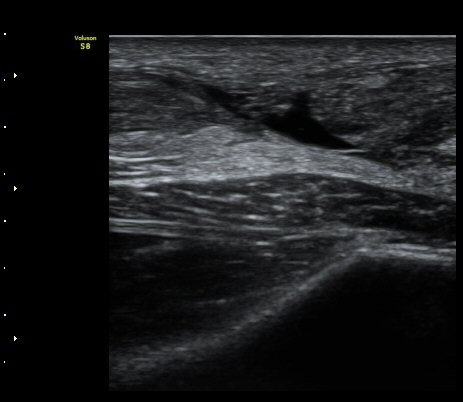

ÃÊÀ½ÆÄ °Ë»ç

d